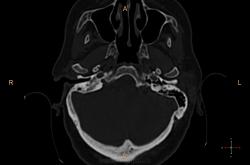

Справа в полости среднего уха небольшое количество жидкости? Пирамида и сосцевидный отросток склерозированы. У нас направляют на КТ только при подозрении на деструкцию или опухоль. Исследование выполняются на специальной программе для височных костей , срезы по 0.1 или 0.05 см, костная структура видна изумительно. А чаще изменения височных костей обнаруживаются как случайная находка при КТ черепа (хорошо видно на "сердечном" режиме).

У нас минимальный срез идет по 0,75мм, мне кажется если есть возможность провести КТ-исследование, следует это делать, что косается данной пациентки, все не так просто, у неё имеется клинически свищ с отделяемым, позади ушной раковины, где имеено и откуда идет свищ четко видно, а так все верно имеется эпитимпанит и антрит.

Согласен, ///если есть возможность провести КТ-исследование, следует это делать///, с Шуллерами-Майерами не сравнить. Кстати, состояние аттико-антральной области обычно более демонстративно на аксиальных срезах уровня латерального полукружного канала.

Касаюсь Андрей Юрьевич, лобарант меня позвал в плане выбора протокола исследования, а я при наложении плоскости сканирование на топограмме, взял и не учел оптико-меатальную линию, получилось несколько неуклюже, поэтому только на станции подорвался выравнивать её при анализе сканов :-(

Свищевой ход.